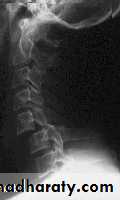

X-rays:

Cervical: 3 views.AP, lateral and open mouth.

Thoraco-lumbar: 2 views.

AP & lateral.

Flexion-Extension views.

CT: best for bony anatomy.

MRI: best to evaluate soft tissue.